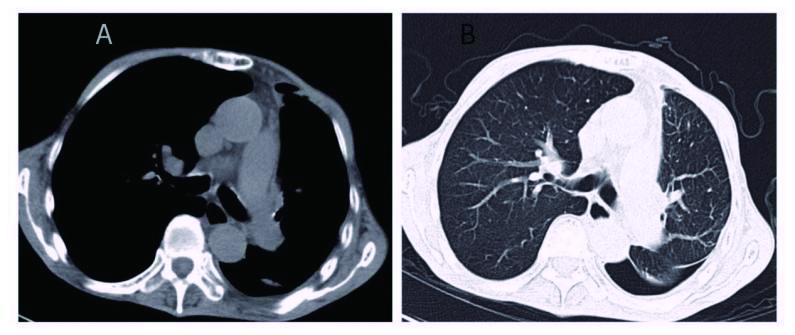

1 资料与方法患者男,70岁,农民,入院前3 d受凉后出现咳嗽,为阵发性干咳、无痰,伴胸闷、气喘,平卧及活动时加重,发热,体温最高37.7 ℃,热型未监测,无畏冷、寒战;当地医院胸部X线平片示左侧胸腔积液、左侧肺炎,予以“头孢噻肟”抗感染治疗无效,于2015年9月29日转来厦门大学附属第一医院。既往慢性支气管炎病史20余年,吸烟史50年×40支/d。入院时查体:T 37.6 ℃,P 106次/min,R 26次/min,BP 118/72 mmHg,SPO2 91%,神志清楚,反应迟钝,有时答非所问,呼吸较急促,气管轻度右偏;左侧胸部呼吸运动减弱,语颤消失,叩诊呈浊音,呼吸音减弱,右肺散在哮鸣音;心界不清,心率106次/min,节律规整,各瓣膜区未闻及杂音。入院后观察患者热型为不规则低热,查血尿粪常规、肝肾功能、肿瘤标志物等正常,降钙素原0.826 ng/mL,结核抗体及结核菌素实验阴性。血气分析:氧分压6.63 kPa,二氧化碳分压正常,无酸碱失衡表现。胸部CT示,双肺多发感染,左侧大量胸腔积液;右肺局限性肺大泡,肺气肿(图 1)。入院后给予莫西沙星抗感染,胸腔穿刺引流出大量淡红色稍混浊胸水,无臭味,每日引流量300~600 mL;胸水常规:李凡他试验阳性,蛋白48.6 g/L,有核细胞数1 520×106/L,比重1.021。患者仍有反复低热,热峰及持续时间稍改善。入院后10 d胸水培养结果回报为星型奴卡菌感染(图 3、4),抗生素更换为TMP-SMX 0.96 g/12 h联合红霉素0.25 g/8 h治疗,体温逐渐下降至正常,咳嗽、气喘症状缓解,胸水引流量逐渐减少至消失,PCT和血气分析结果恢复正常,胸部CT:左侧少量胸腔积液,伴积气(图 2)。于2015年10月25日出院,继续口服TMP-SMX片及红霉素片治疗,定期随诊。患者感觉恢复良好在出院后1个月左右自行停药,3个月后因右侧肢体无力再诊我院,颅脑MRI提示:大面积小脑梗死,脑疝并幕上脑积水(图 5),再诊时未再复查胸部CT,2 d后因呼吸循环衰竭死亡,家属未同意尸检。

| 图 2 胸腔穿刺术后,可见左肺复张,双肺纹理清晰,伴少量积气(A:纵隔窗; B:肺窗) |